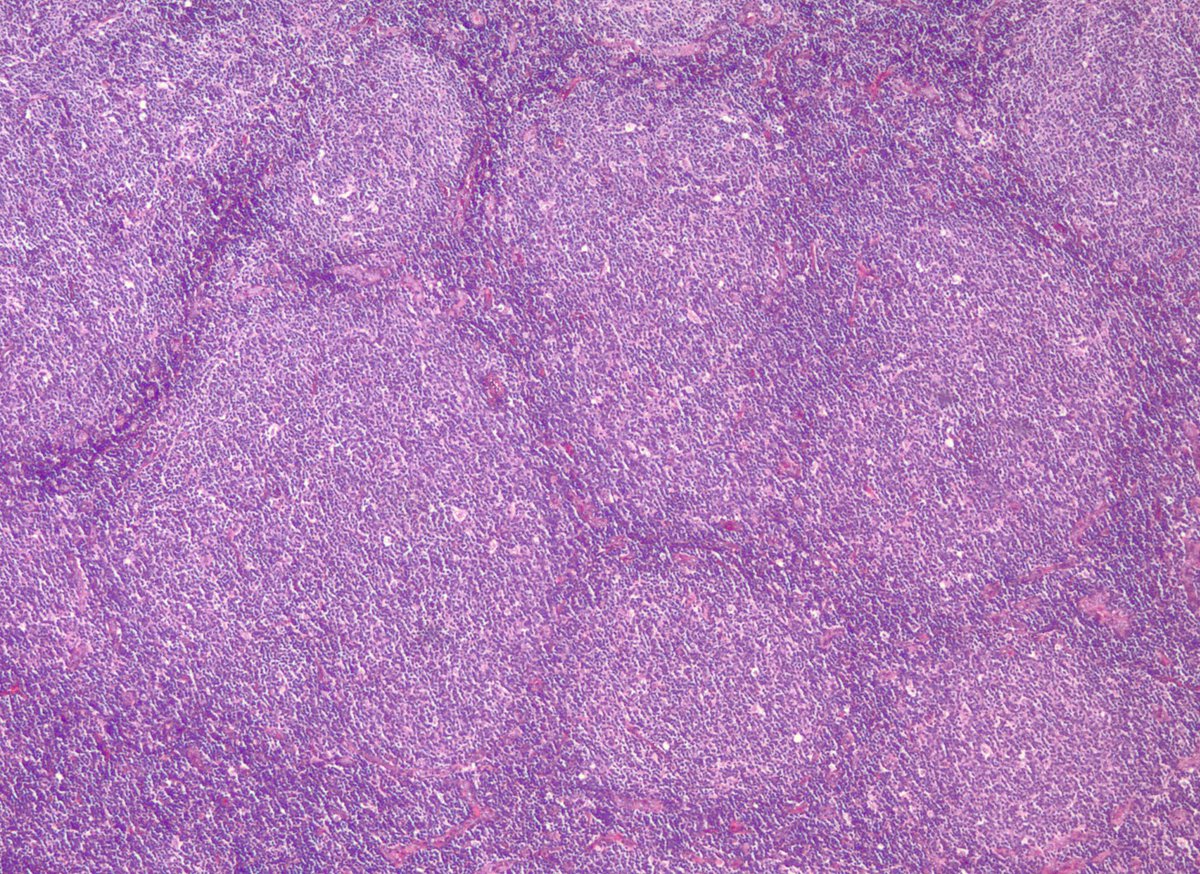

Some follicular lymphomas may appear to be BCL2-negative with commonly used IHC antibodies. Some of these cases have mutations in BCL2 that impact protein detection. Alternate BCL2 clones may be useful, as in this case. onlinelibrary.wiley.com/doi/full/10.10… #pathology #hemepath

jake_bledsoe's tweet image. Some follicular lymphomas may appear to be BCL2-negative with commonly used IHC antibodies. Some of these cases have mutations in BCL2 that impact protein detection. Alternate BCL2 clones may be useful, as in this case.